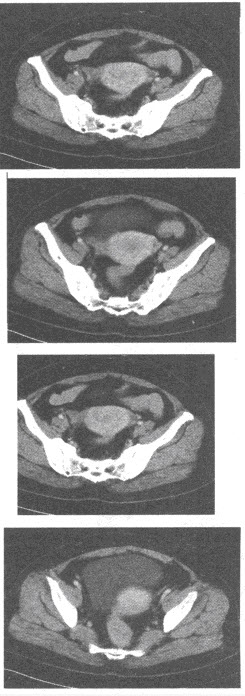

男,67岁,排尿不畅、无力伴血尿1周。直肠指检前列腺增大、质硬。PSA>100ng/ml。根据所提供的增强CT图像,最可能的诊断是()

CT平扫如下图所示,符合下列哪种诊断()